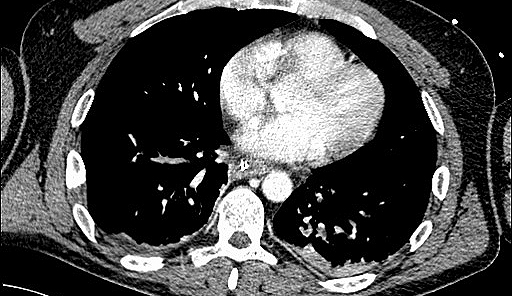

Umgekehrt kann es jedoch auch im Rahmen einer akuten Nierenschädigung zu einer zunehmenden Schädigung und Funktionseinschränkung der Lunge kommen. „Dies kann zum Beispiel durch einen Flüssigkeitsüberschuss bedingt sein, wenn die Niere aufgrund ihrer Schädigung eine adäquate Flüssigkeitsausscheidung nicht mehr aufrechterhalten kann. In weiterer Folge kann dies ein Lungenödem zur Folge haben“, erklärt Intensivmediziner Joannidis. Durch entsprechende vorsichtige Flüssigkeitsbilanzierung beziehungsweise Unterstützung der Flüssigkeitsausscheidung mit harntreibenden Medikamenten oder Nierenersatztherapie (Dialyse) könne dieser Komplikation, so ein Ergebnis der Untersuchung, vorgebeugt werden. Des Weiteren konnten verschiedene Effekte von extrakorporalen Systemen, wie eine „künstliche Niere oder Lunge“, auf die Organfunktionen aufgezeigt werden. „Insbesondere die Kombination von extrakorporalen Systemen stellt Ärztinnen und Ärzte vor neue Herausforderungen und Fragestellungen, wodurch auf diesem Gebiet sich einige neue Forschungsfragen ergeben haben“, sagt Michael Joannidis. So konnten insgesamt mit Ergebnissen der Untersuchung sowohl Empfehlungen für die direkte PatientInnenenversorgung als auch weitere Fragestellungen für zukünftige Forschungsschwerpunkte formuliert werden.